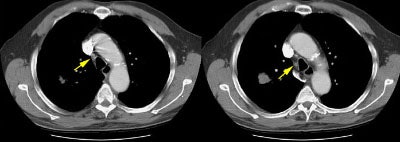

Example 2: This patient is an example of a false negative CT for hilar nodal metastases even when applying the suggested new criterion. The patient had a peripheral adenocarcinoma in the left upper lobe (black arrows). The left hilar node (yellow arrows) is not pathologic by size criteria, nor does it exhibit a convex margin with the adjacent lung parenchyma. This is a normal node by CT, however, at histopathologic analysis the node was positive for malignant cells.